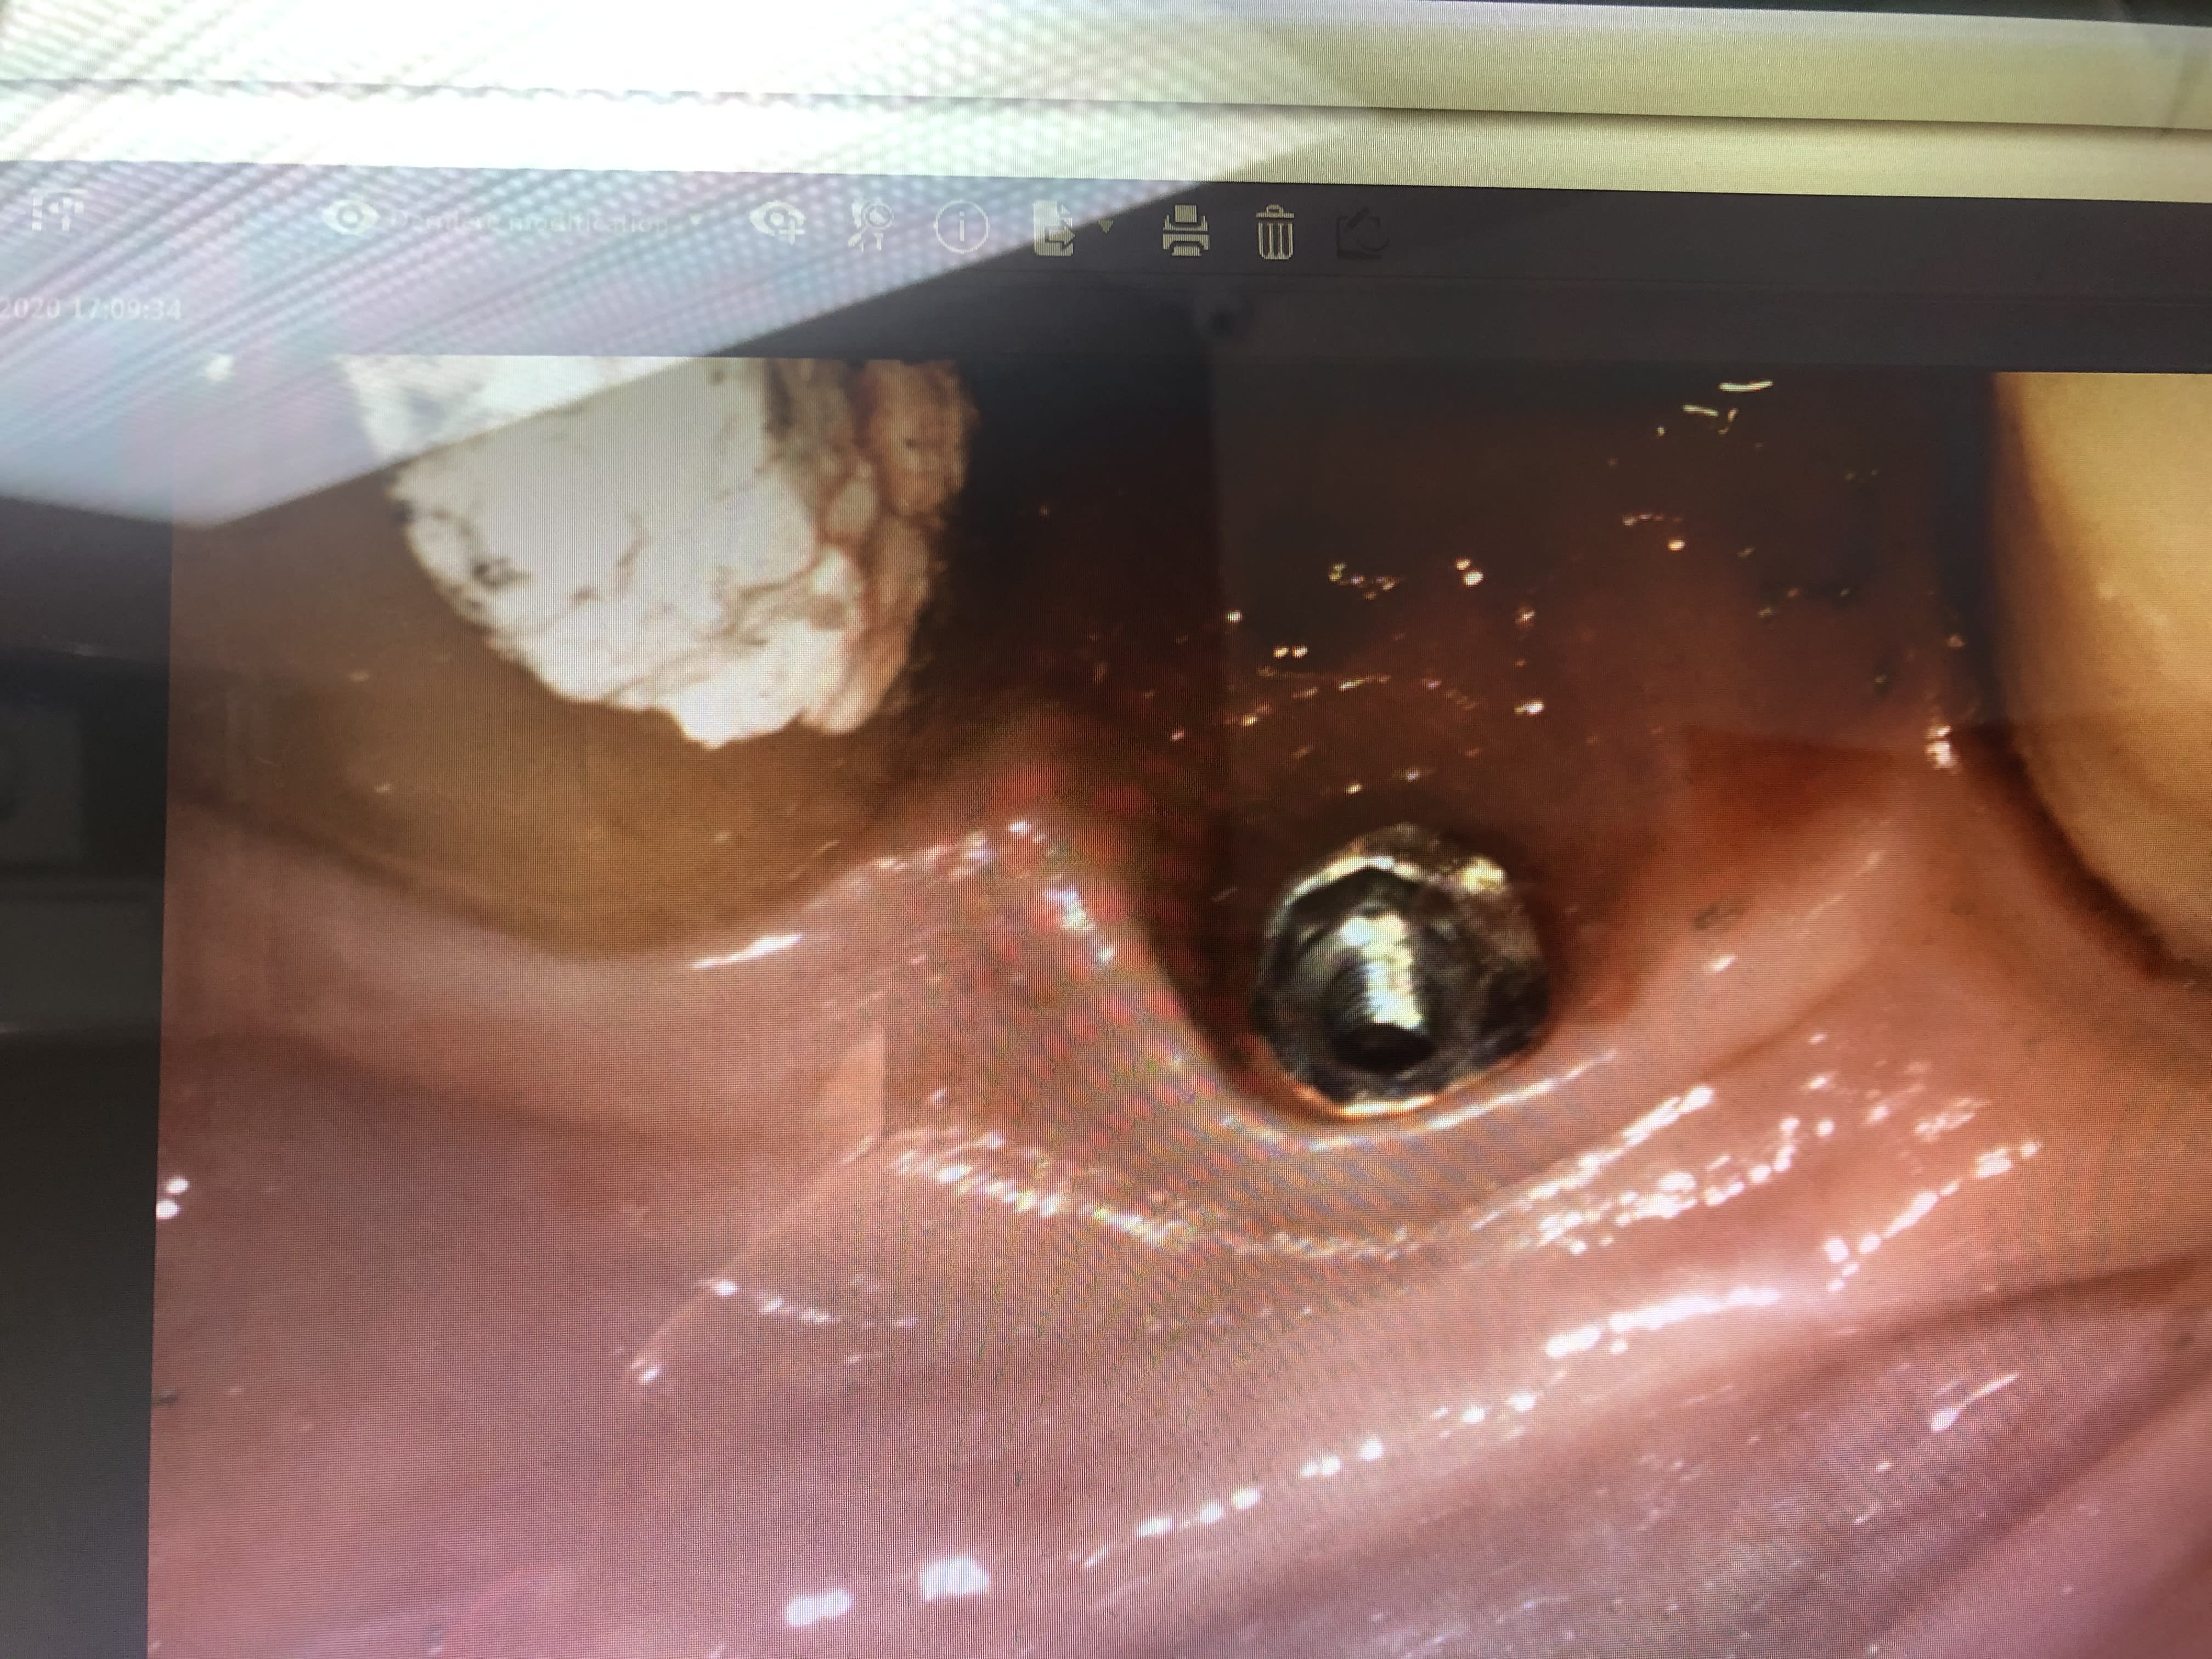

J’ai besoin de votre aide pour identifier cet implant...

implant très caractéristique à l'apex avec ses 4 trous et apex plat: TBR

http://osseosource.com/dental-implants/product_info.php?manufacturers_id=38&products_id=436